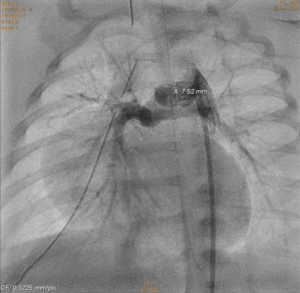

Noworodek z zarośnięciem zastawki płucnej bez ubytku przegrody międzykomorowej i hipoplazją prawej komory serca;

A – pomiary średnicy przewodu tętniczego w aortografii;

B – stan po implantacji stentu do przewodu tętniczego.